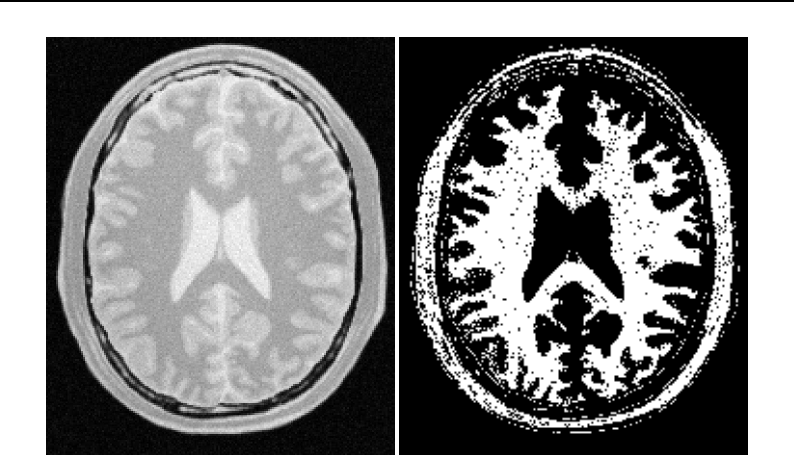

- Casting and Intensity Mapping

- Thresholding